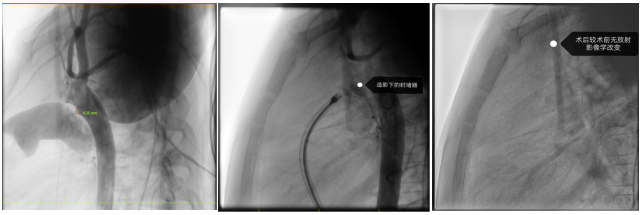

由于患者年仅4岁,经团队评估后,适合选择介入无金属植入物的全降解封堵器封堵治疗。目前的全降解封堵器由生物高分子材料组成,配合三层阻流膜设计,可有效降低残余分流的风险,且后续无金属植入物在体内,大大减少对未来生活、工作、心理等影响。

在张智伟教授指导下,玉溪市人民医院心内科团队手术过程中,精准定位动脉导管分流位置,将生物可降解封堵器成功植入,实现了对分流的有效封堵。术后超声评估封堵器周围无残余分流,封堵器占位良好。